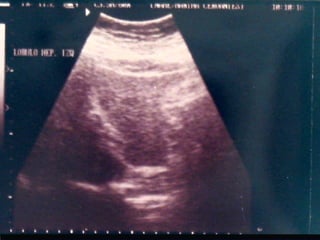

SONOGRAMA ABDOMINAL EVALUACIÓN TAMAÑO ( Hepatitis, I.C.C., Cirosis) FORMA (lobular en cirrosis) LOCALIZACIÓN ( de masas) PATRON SONOGRÁFICO ( hiperecoico gris)

SONOGRAMA ABDOMINAL EVALUACIÓN HIGADO SISTEMA BILIAR BAZO  RIÑONES PANCREAS ( no específico)

SONOGRAMA ABDOMINAL EVALUACIÓNTAMAÑO ( Hepatitis, I.C.C., Cirosis) FORMA (lobular en cirrosis) LOCALIZACIÓN ( de masas) PATRON SONOGRÁFICO ( hiperecoico gris)

SONOGRAMA ABDOMINAL EVALUACIÓNHIGADO SISTEMA BILIAR BAZO RIÑONES PANCREAS ( no específico)